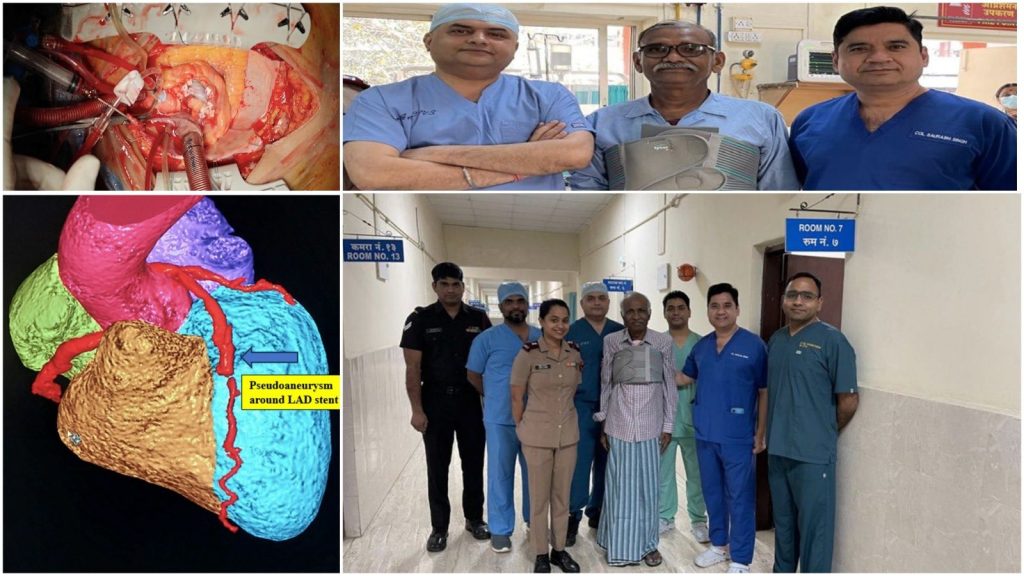

AICTS Pune Achieves Rare Global Milestone in Cardiac Surgery

PUNE – In a remarkable display of surgical precision and clinical excellence, doctors at the Army Institute of Cardiothoracic Sciences (AICTS) in Pune have successfully treated four patients suffering from an ultra-rare cardiac complication. This achievement places the premier military institute at the forefront of global cardiac care, as only about 40 such cases have been documented worldwide.

All four patients have shown successful resolution of the complications, a testament to the advanced critical care capabilities of the Armed Forces Medical Services (AFMS).

A Landmark for Southern Command

The Southern Command of the Indian Army lauded the feat, noting that such success in treating a condition with so few global precedents reflects the exceptional expertise of military “doctors in uniform.”

The AICTS continues to serve as a beacon of advanced medical research and high-end surgical intervention, reinforcing Pune’s reputation as a major hub for specialized healthcare in India.